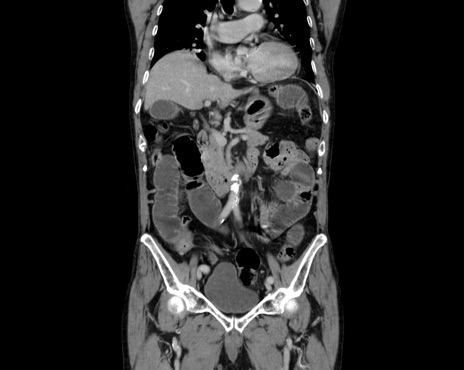

症例26(冠状断像)

【症例】80歳代男性

【主訴】嘔吐

【現病歴】昨晩2回嘔吐あり、今朝になっても嘔吐あり。来院。

【既往歴】胃潰瘍

【身体所見】意識清明、BT 37.6℃、BP 166/95mmHg、HR 100bpm、SpO2 97%、腹部:平坦・軟、腸蠕動音聴取良好、圧痛なし。

【データ】WBC 21900、CRP 1.4